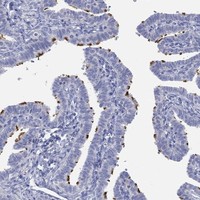

Immunohistochemical staining of human fallopian tube shows strong membraneous positivity in glandular cells.